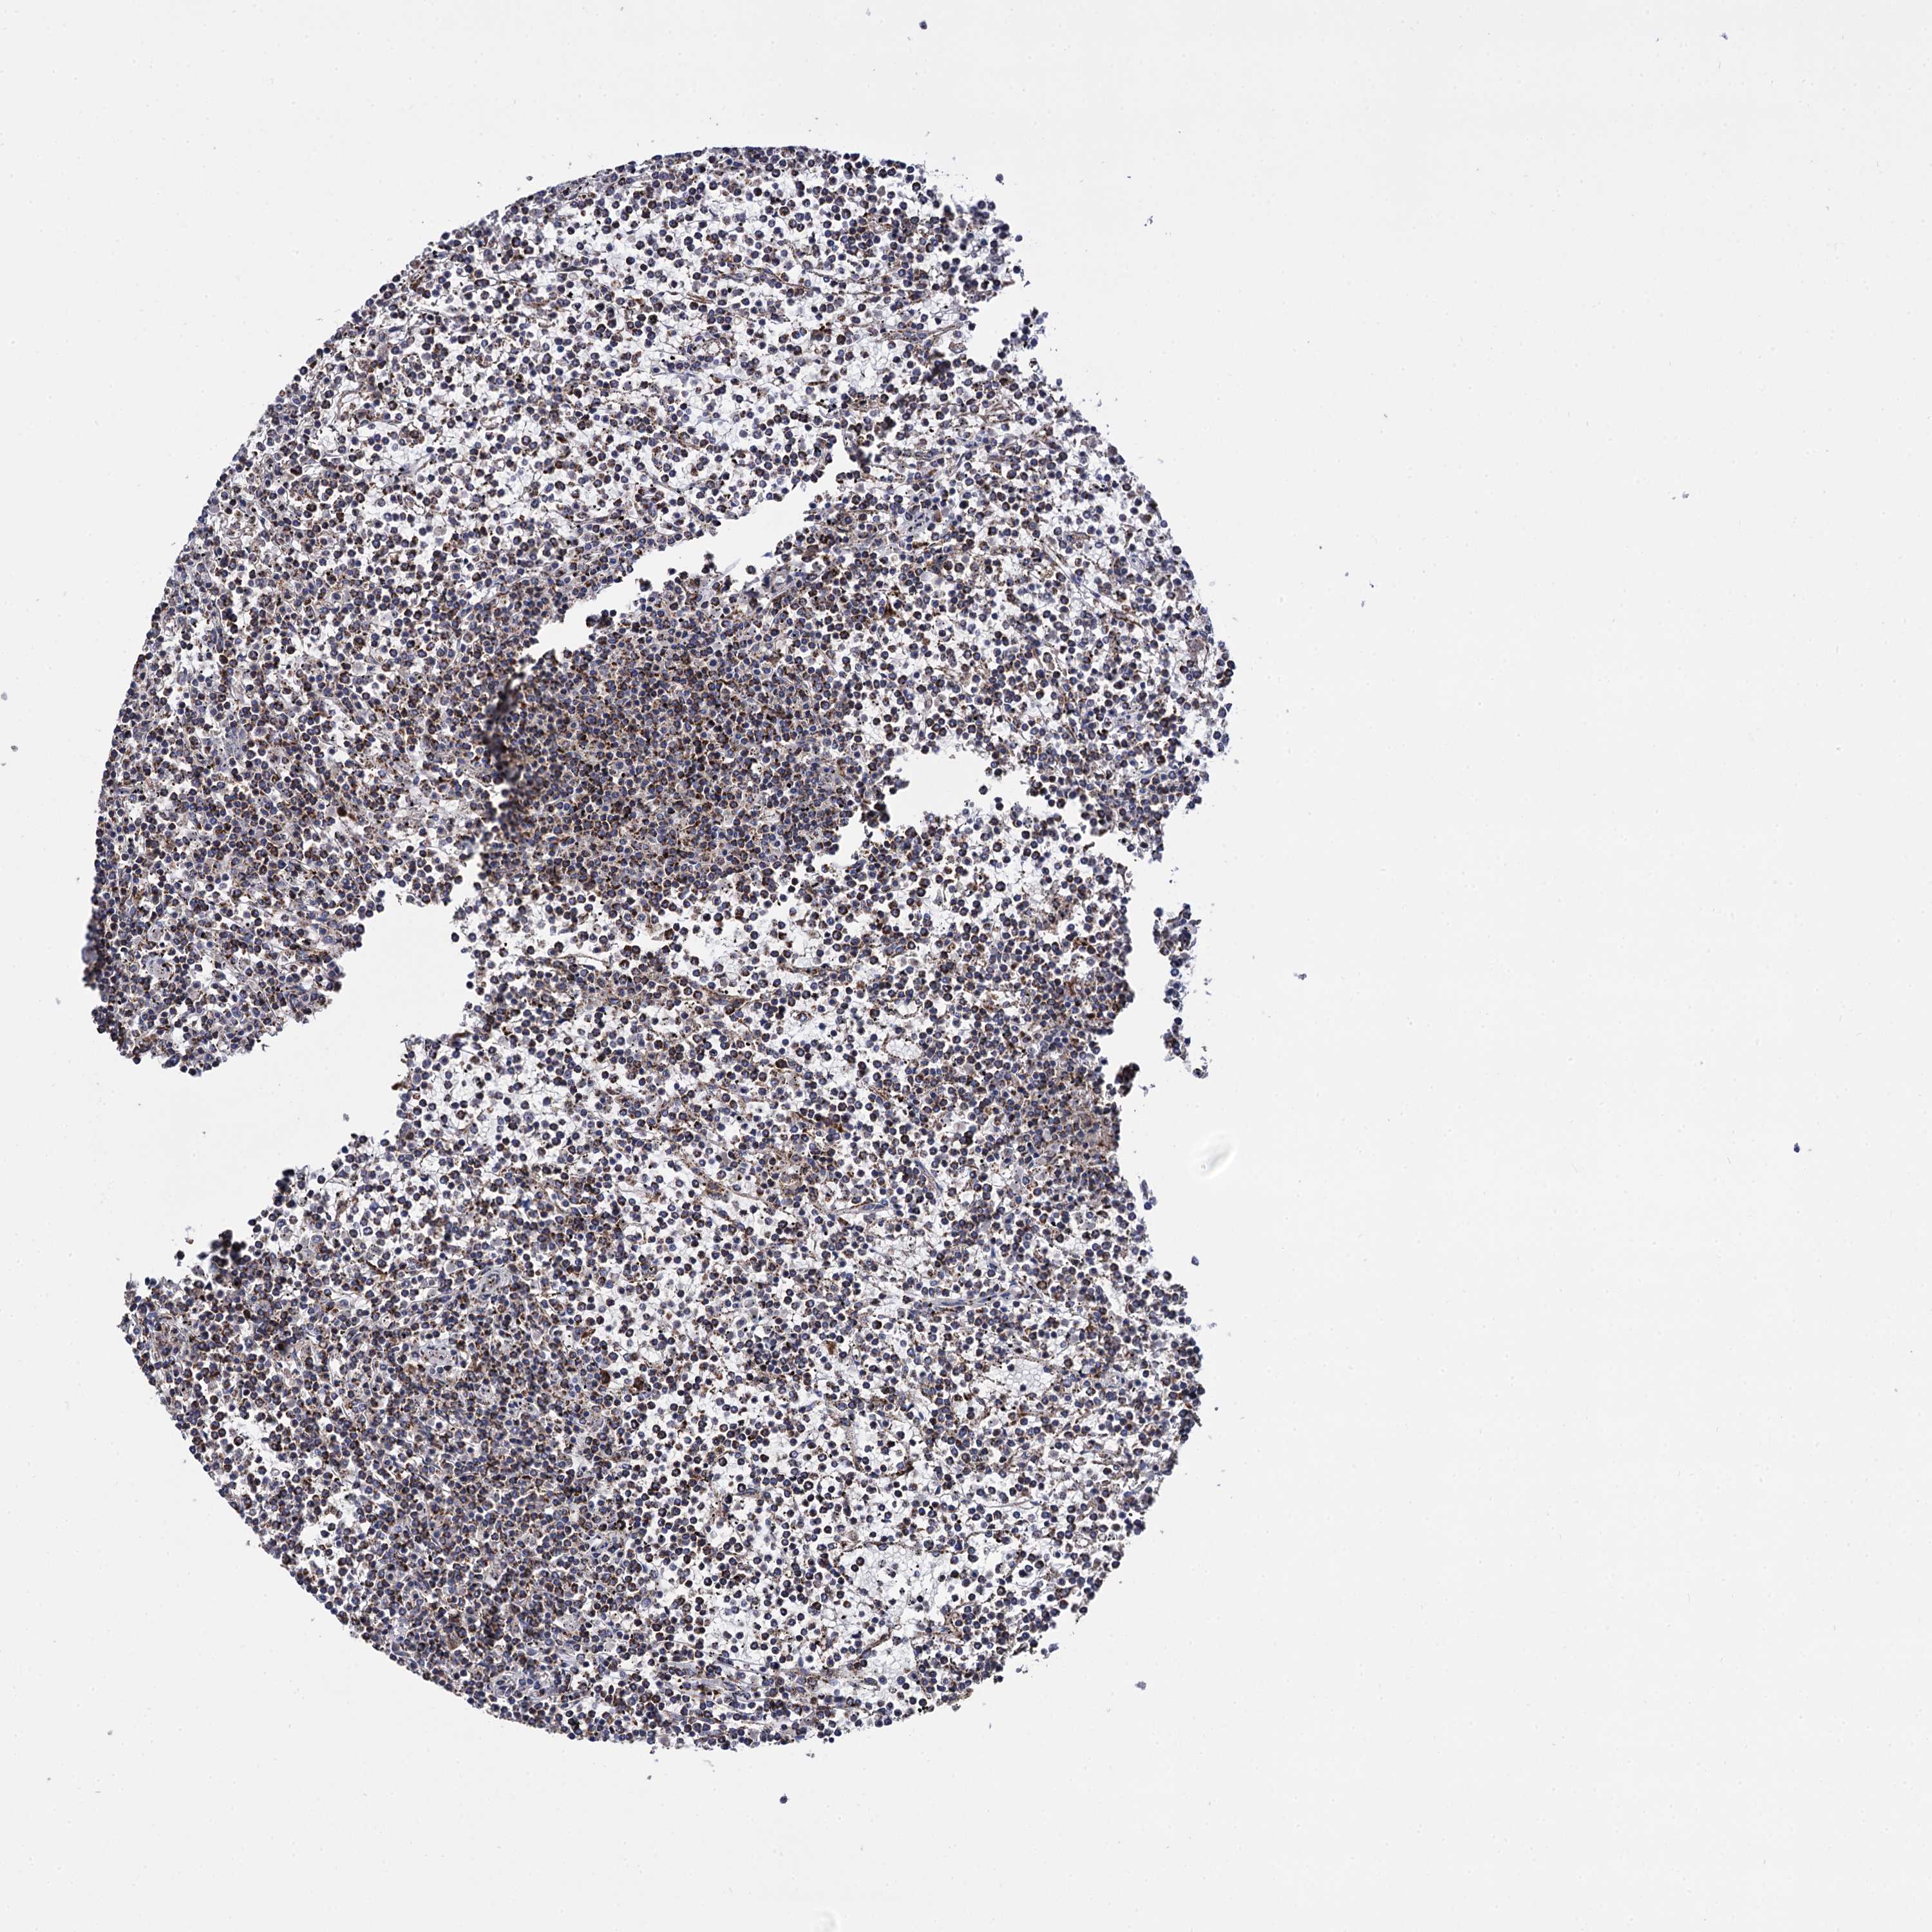

CANCER LYMPHOMA Show tissue menu

LYMPHOMA - Protein expressioni

A mouse-over function shows sample information and annotation data. Click on an image to view it in a full screen mode. Samples can be filtered based on level of antibody staining by selecting one or several of the following categories: high, medium, low and not detected. The assay and annotation is described here.

Each image is clickable and will lead to virtual microscopy that enables deeper exploration of all samples and also displays staining intensity scores, fraction scores and subcellular localization as well as patient and tissue information for each sample.

Antibody HPA040845

Staining

High

Strong

>75%

Location

Nuclear

Hodgkin's disease, NOS

Malignant lymphoma, non-Hodgkin's type, High grade

Malignant lymphoma, non-Hodgkin's type, Low grade